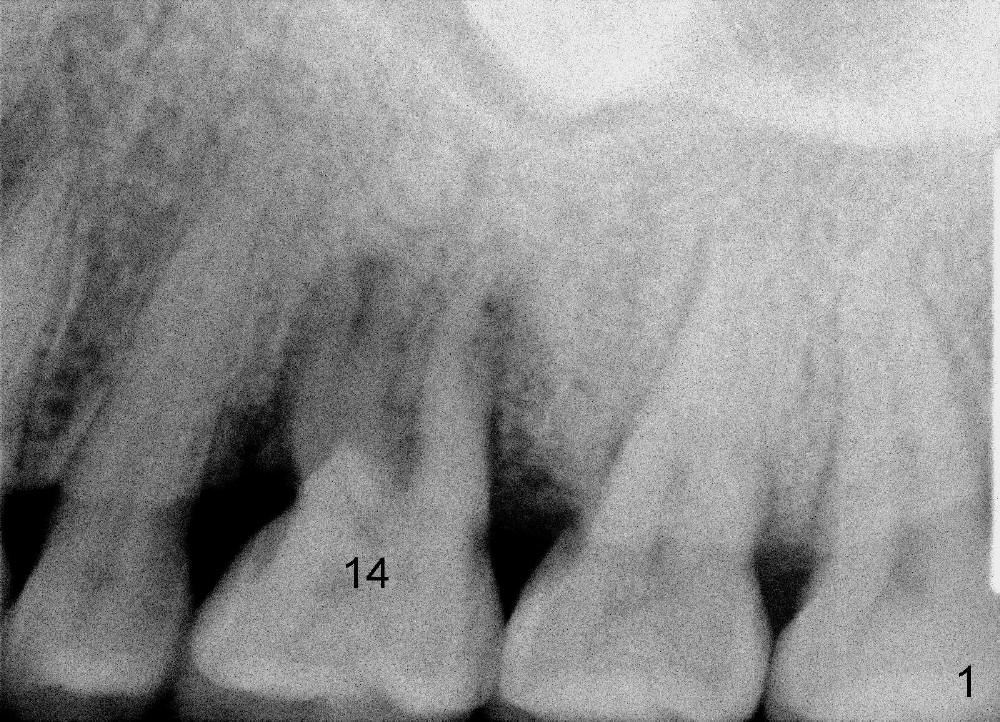

A 46-year-old man returned to clinic last year with chief complaint "Top left molar becomes loose suddenly". The mesiobuccal pocket was deep. He had had history of chronic periodontitis and was in perio maintenance program. PA reveals radiolucency around the 1st molar roots (Fig.1: #14). What else does it show, as related to immediate implant?